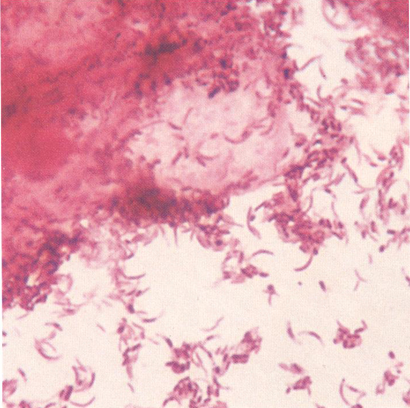

Fig. 21.5.5.1: Lactobacillus spp. (coloratie Gram, x1000, imagine din colectia proprie a laboratorului)

Aspect normal al unui prelevat vaginal: prezenta a numeroase celule epiteliale pavimentoase, polimorfonucleare putine, bacili Doderlein